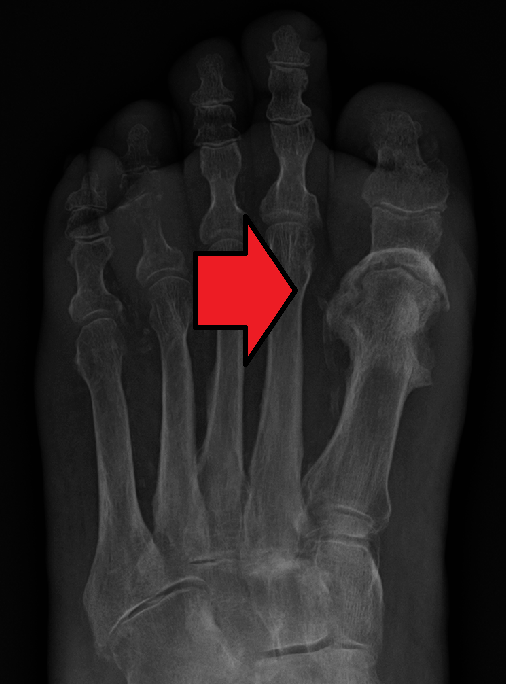

Chondroma

Chondromas are benign tumors composed of cartilage.

Chondromas typically develops in the medulla of the small bones in the hands and feet.